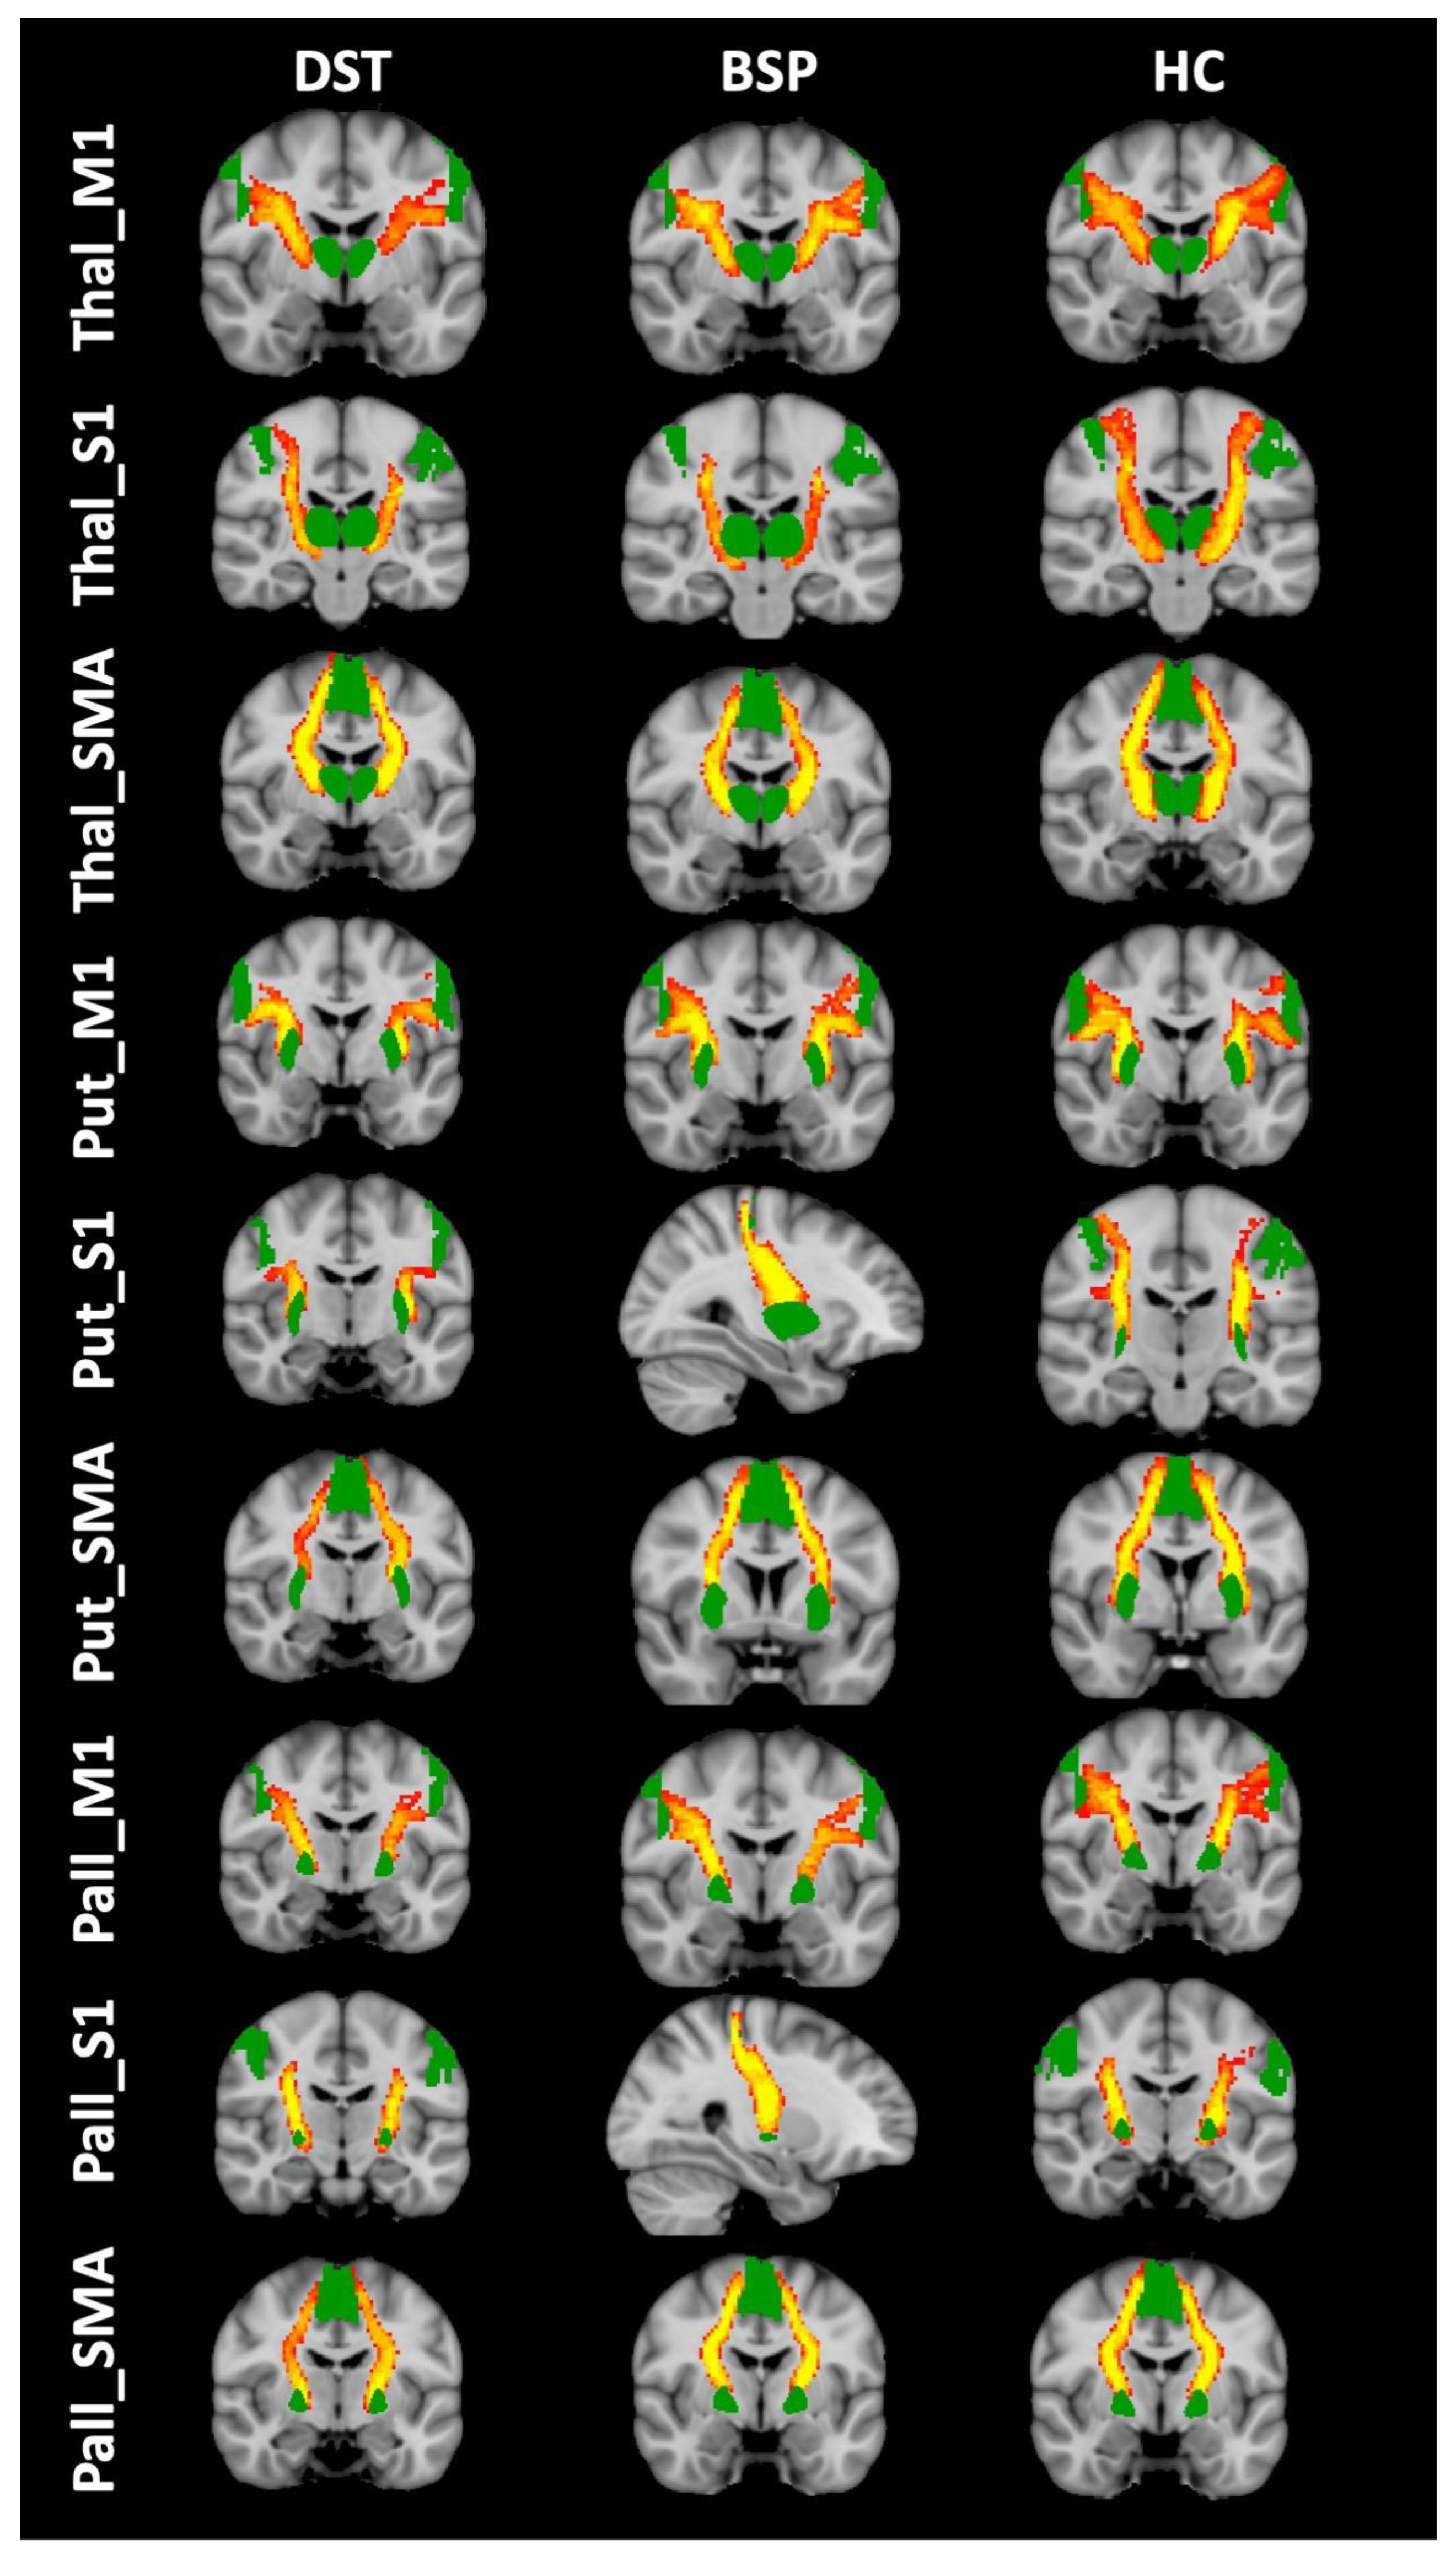

2.3.2. Tractography